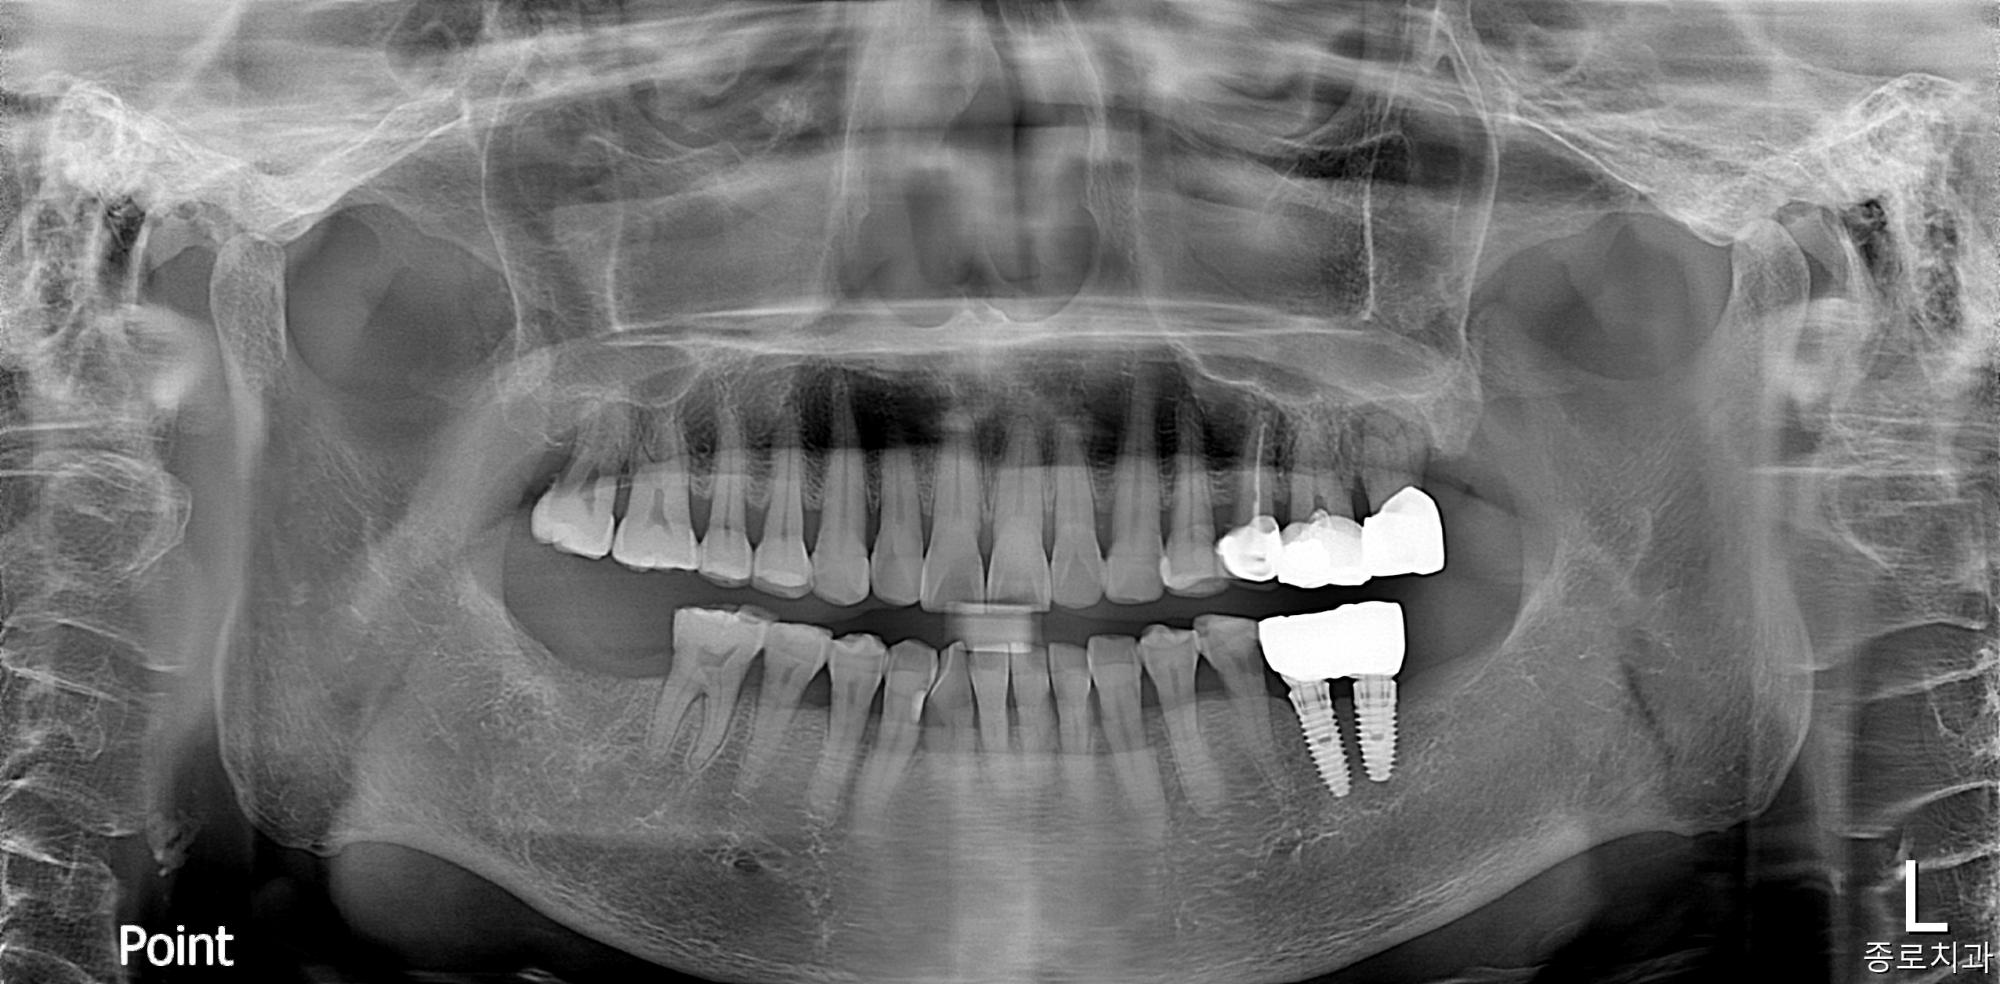

전/후사진

전/후 사진갤러리